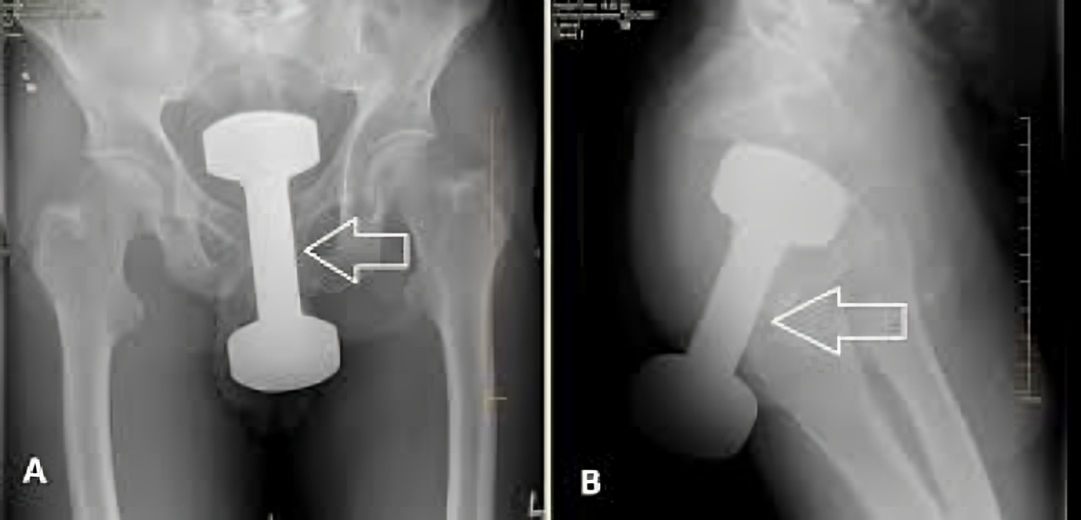

BRAZIL: In an extraordinary and unsettling case, a physician disclosed that a 2.5-kilogram dumbbell was surgically removed from a patient’s body. What stunned the medical team even more was the patient’s refusal to explain or admit how the object got there.